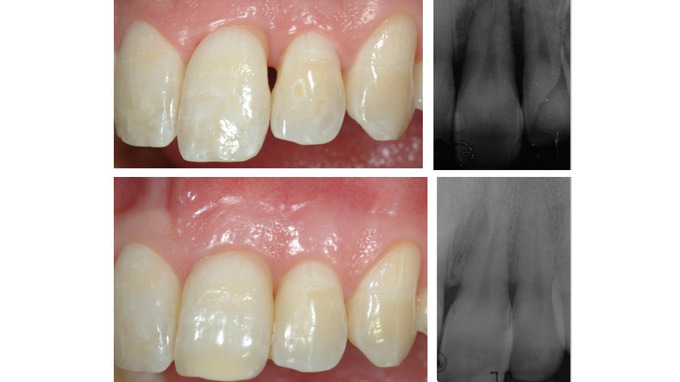

Traditionnellement, les résultats d’une thérapeutique de régénération parodontale étaient évalués par le comblement du défaut osseux d’un point de vue radiographique et par le gain d'attache clinique.

Aujourd'hui, au niveau des zones esthétiques, ces aspects ne suffisent plus. L'amélioration de l'esthétique des tissus mous associée à la régénération parodontale, est primordiale.

Une nouvelle procédure, combinant une technique de préservation papillaire avec greffe de tissu conjonctif et lambeau déplacé coronairement, sera présentée. La greffe de tissu conjonctif joue le rôle de paroi vestibulaire du défaut intra-osseux, traité par apport d’amélogénines, augmentant ainsi la stabilité du caillot

sanguin pour favoriser la régénération parodontale et améliorer le résultat esthétique.